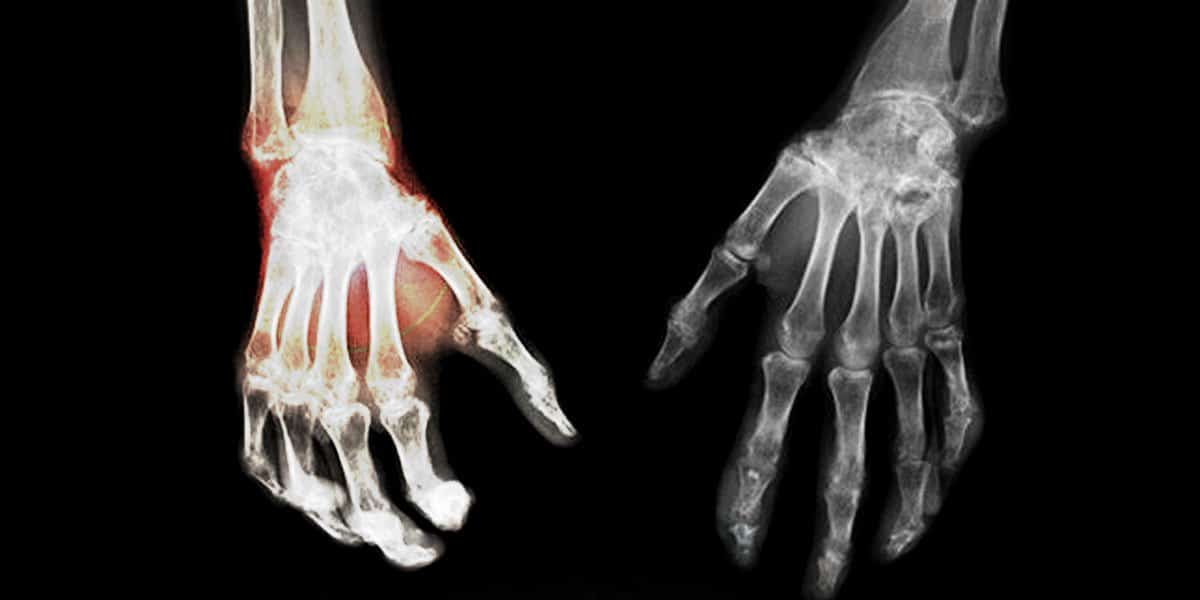

Le syndrome douloureux régional complexe (SDRC) est un trouble neurologique antérieurement appelé « dystrophie sympathique réflexe ». Les patients souffrant de SDRC éprouvent de la douleur chronique dans une certaine partie de leur corps. La douleur peut commencer après une entorse mineure ou après avoir subi une simple chirurgie. Mais qui apparaît beaucoup plus grave que ce à quoi on pourrait s’attendre en considérant la blessure originale. Le récepteur cannabinoïde 2 (CB2) est apparu comme une cible prometteuse pour le traitement de différents syndromes douloureux neuropathiques comme la SDRC

- Une diminution de la densité osseuse (et de possibles fractures)